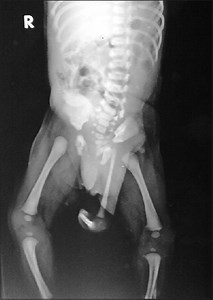

Polymelia - Alchetron, The Free Social Encyclopedia

Polymelia adalah cacat lahir genetik dan jenis cacat bawaan anggota badan yang kadang-kadang dapat terjadi pada ayam, dan didefinisikan sebagai pertumbuhan anggota badan tambahan yang melekat pada berbagai daerah tubuh. Penyebab anomali kongenital ini tidak diketahui, namun diduga terkait dengan faktor genetik atau kemungkinan terapar toksin di lingkungan. #teratologi #genetika #biologi #generasibiologi #biology Credit unknown, please DM for credit or removal! Disclaimer: this content for educat

Polymelia is a rare condition where a baby is born with extra arms or legs. Key points: • The extra limbs can be fully formed or only partly developed. • It can happen because of problems during early development, genetic changes, or if twins don’t fully separate (the extra limb may come from a “parasitic twin”). • Doctors can often see it before birth using ultrasound or MRI. • Surgery is usually done in early childhood to remove the extra limb for better movement and appearance. #reelsfbシ #hig

Polymelia in chicken; A rare Congenital anomaly#chickenhealth#poultryhealth #chicken